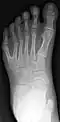

Полидактили́я (др.-греч. πολύς — много + δάκτυλος — палец, синоним — многопалость), также известная как гипердактилия — порок развития, характеризующейся бо́льшим, чем в норме, количеством пальцев на руках или ногах у человека, собак, котов и лошадей. Противоположным отклонением является олигодактилия.

У людей и животных она может проявляться как на одной, так и на обеих руках. Обычно дополнительный палец представляет собой небольшой кусочек мягкой ткани, которую можно удалить. Иногда это просто кость без суставов; очень редко лишний палец бывает полноценным. Дополнительный палец чаще всего образуется со стороны мизинца, реже - на стороне большого пальца и очень редко - между средними пальцами. Обычно лишний палец является аномальным разветвлением обычного пальца, редко возникает на запястье, как обычный палец.